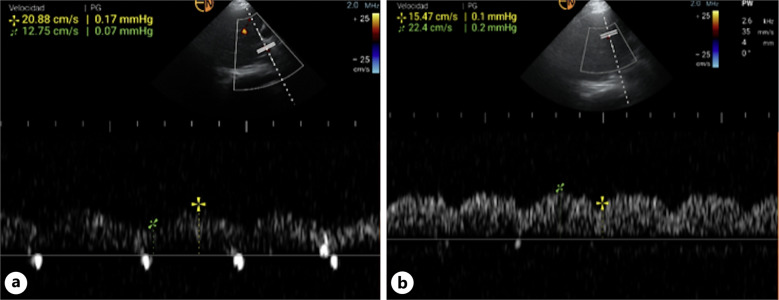

Case presentation: A 37-year-old previously healthy male presented with a gunshot wound to the left leg, resulting in significant vascular injury and hemorrhagic shock requiring surgical intervention. Postoperatively, the patient remained intubated and hemodynamically unstable, developing stage 3 acute kidney injury necessitating continuous renal replacement therapy (CRRT). Due to further deterioration and the need for amputation, the patient was confined to the operating room (OR), where CRRT could not be performed. Given the patient's anuria and fluid overload, the nephrology team assessed the patient and determined he was a suitable candidate for manual dialysis using the Kirpa Kit™, with ultrafiltration (UF) as the primary objective for fluid removal. A total of 600 mL of UF was safely removed (UF rate of 600 mL/h), and the patient demonstrated both clinical and ultrasonographic improvement. Notably, portal vein pulsatility decreased from 38% to 31% following the procedure, indicating a reduction in fluid overload. The patient's vital signs remained stable throughout.